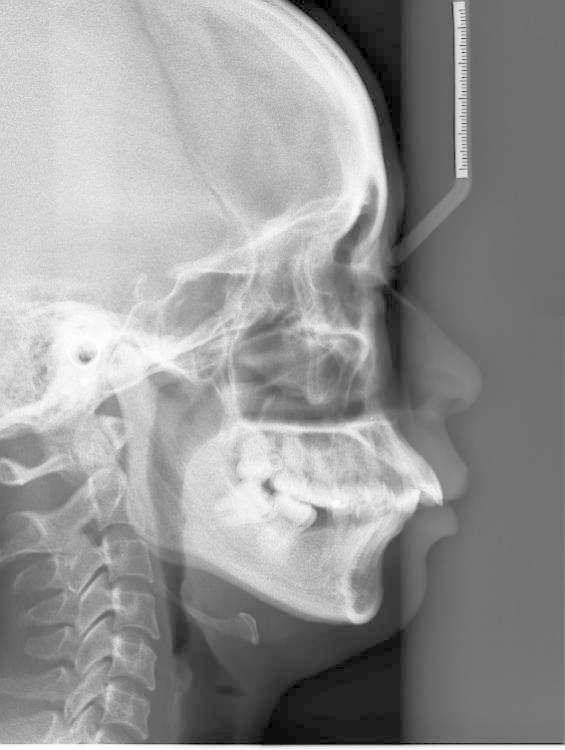

牙齿矫正,其原理就是牙槽骨改建的过程,利用的就是牙齿移动、牙槽骨跟随生长的机制。具体做法就是医生通过矫治器给牙齿施加一个外力,牙齿就会在牙槽骨里缓慢移动,受力侧牙槽骨吸收,受到牵引的一侧牙槽骨增生,以保持牙槽骨正常厚度。此消彼长,所以牙齿是不会松动的。PART 02

首先我们看能不能矫正,不是单纯靠年龄来判断,并不是年龄大的就不能矫正,年龄小的就一定能做。限制牙齿移动的关键不是年龄,而是牙周的健康状况。当然,除了牙周的健康程度外,我们还得考虑牙齿的健康程度、关节的健康程度,以及配合度等问题。在排除以上问题后我们还是建议大家尽早解除自己的牙齿问题的。

年龄虽然不是限制整牙的关键因素,但成人矫正还是有自身限制的。成人毕竟不像小朋友一样,有非常旺盛的生长潜力,那么我们成年人治疗的目标有时相对而言就要放得保守一点,尤其对有骨性问题,牙周不那么健康,关节不那么健康的人而言就不能事事追求完美。